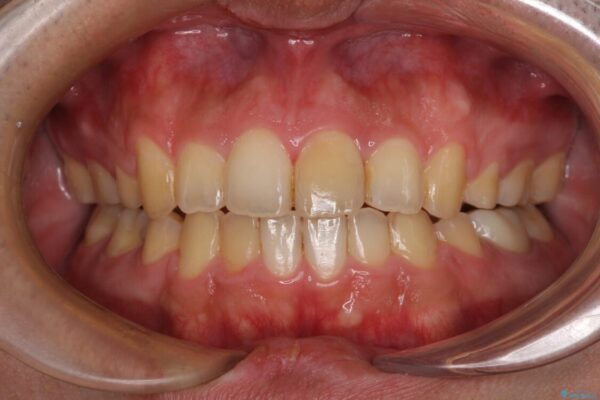

治療前

• 後戻りでデコボコの前歯 インビザライン矯正治療 治療前画像